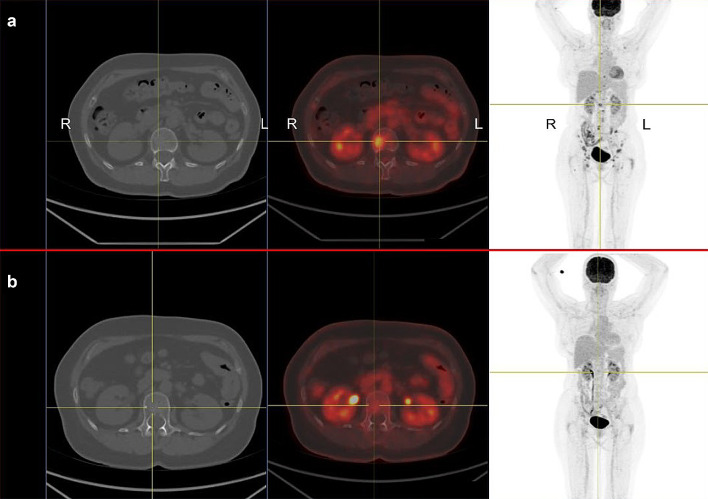

Patient 1 A 61-year old woman was diagnosed with uveal melanoma in March 2012, which was treated with proton beam therapy, which lead to complete tumor remission. After several years of asymptomatic follow-up examinations in our oncological department she reported to have increasing back pain that did not subside during periods of resting (Fig. 1a). A PET-CT scan in November 2016 showed metastatic cancer with extensive spread to several bones, including the spine. Tumor biopsy confirmed metastatic melanoma. The patient also suffered from RRMS and has been on treatment with fingolimod since 2013. Due to new metastatic disease fingolimod was stopped in January 2017. Despite the risk of MS flare-up during ICI treatment she received anti-PD1 treatment with pembrolizumab in January 2017, which showed excellent response (Fig. 1b). After an initial response, she developed new bone metastases in July 2017 and was switched to anti-CTLA4 treatment with ipilimumab. The first biopsy was obtained during fingolimod treatment and revealed very sparse lymphocytic infiltrate, as shown in Fig. 2a–d and in Fig. 3a, b. Interestingly, a follow-up biopsy taken after stopping fingolimod and during pembrolizumab treatment showed significantly more lymphocytic infiltration compared to the first biopsy (Fig. 3c, d), indicating immune system invigoration against the tumor. The patient showed good therapy response to ipilimumab and has not experienced any MS flares during or after therapy.

Fig. 1.

Relapsing metastatic melanoma and response to anti-PD1 treatment in a patient with fingolimod. a 18F-FDG PET/CT scan shows multiple bone metastases of melanoma, including the spine (centered by yellow crosshair). The patient has relapsing-remittent multiple sclerosis (RRMS) and is under treatment with fingolimod. R right, L left. b After ceasing fingolimod and starting treatment with pembrolizumab the follow-up PET/CT scan after 12 weeks shows a partial remission of all bone metastases including the spine. To date the patient showed no flares of RRMS, despite complete cessation of fingolimod